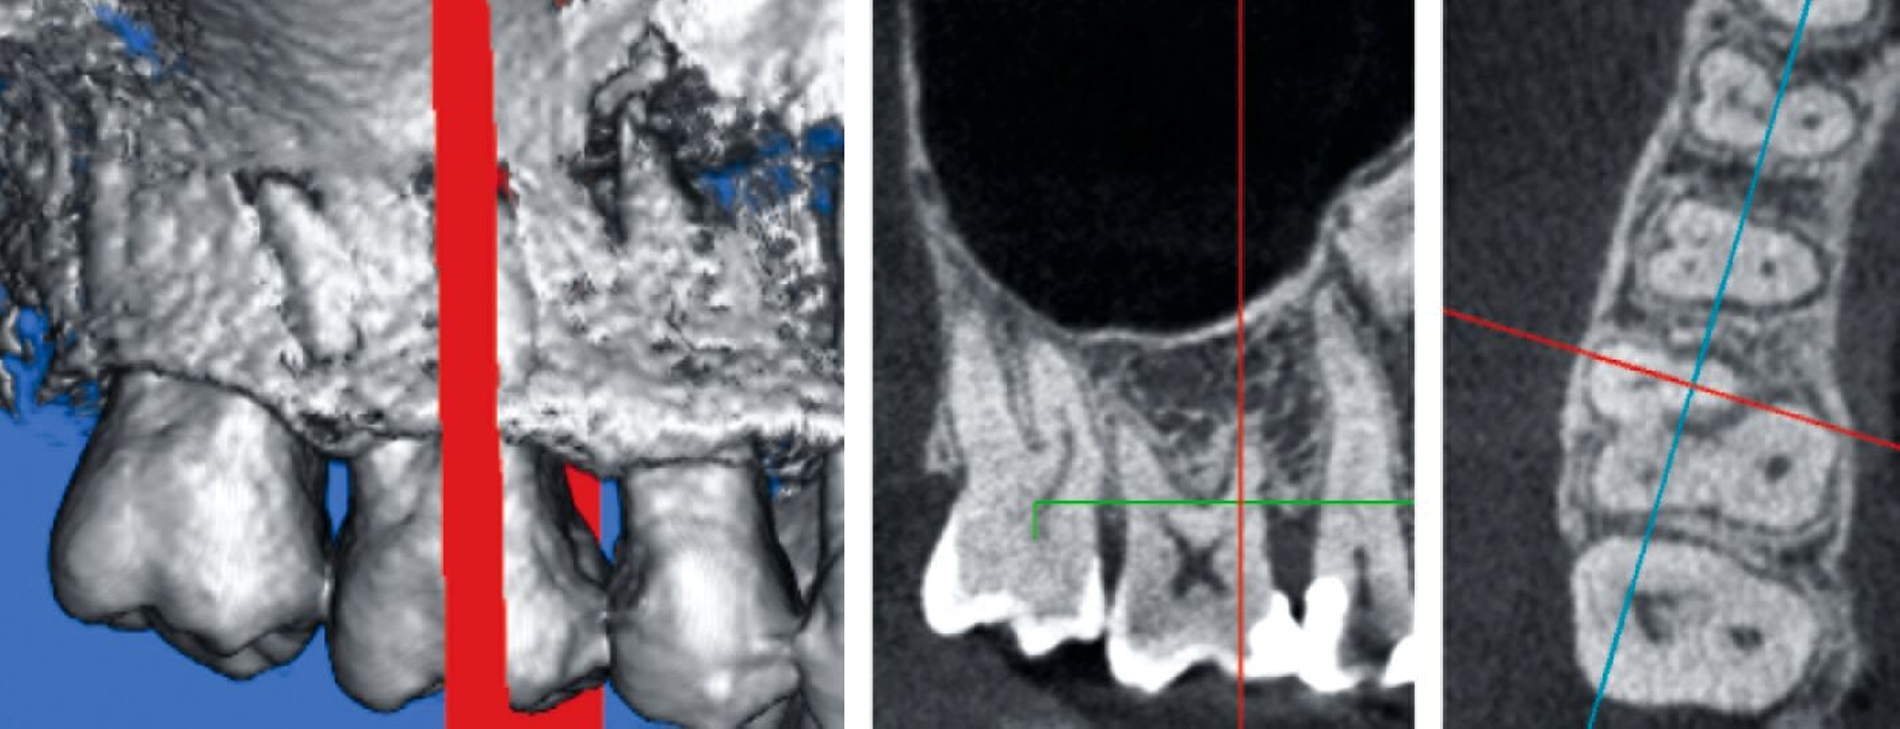

Da der histologische Nachweis einer erfolgreichen Furkationsregeneration kein praktikabler Endpunkt für kontrollierte klinische Studien ist, dienen Veränderungen bei direkten Knochenmessungen (offene Messungen: horizontales Knochensondierungsniveau bei der Operation und während eines „Re-entry“-Eingriffs) als primäre Ergebnisvariablen zur Bewertung des klinischen Erfolgs, während geschlossene Messungen wie der klinische Attachmentgewinn (horizontales/vertikales Attachmentniveau (CAL)), die Reduktion der Taschensondierungstiefe (TST) und röntgenologische Beurteilungen als sekundäre Zielparameter dienen können [Machtei, 1997]. Zu den von den Patienten berichteten Ergebnissen nach einer regenerativen Furkationschirurgie können postoperative Schmerzen, die Komplikationsrate, der wahrgenommene Nutzen und die Veränderung der Lebensqualität gehören.

Systemische Faktoren, die den Erfolg regenerativer Maßnahmen beeinflussen können, sind beispielsweise ein unkontrollierter Diabetes oder eine eingeschränkte Immunabwehr. Verhaltensfaktoren wie Rauchen, unzureichende Mundhygiene und mangelnde Adhärenz müssen ebenfalls bei der Fallauswahl berücksichtigt werden. Zu den anatomischen beziehungsweise Defektfaktoren, die sich einigen Studien zufolge und nach Expertenkonsens negativ auf die Erfolgsaussichten einer regenerativen Furkationstherapie auswirken können, werden gezählt: ein erschwerter Zugang zum Operationsbereich, ein approximales Knochenniveau, das sich auf derselben Höhe oder sogar apikal des Furkationsdaches befindet, ein kurzer Wurzelstamm, ein enger Abstand zwischen den Wurzeln mit erschwerter Instrumentierung, eine deutlich erhöhte Zahnbeweglichkeit, ein dünner gingivaler Phänotyp, wenig keratinisiertes Gewebe, die Nähe eines Restaurationsrandes zum Furkationseingang und das Vorliegen einer gingivalen Rezession im Furkationsbereich.

Ein adäquater Zugang zum Operationsbereich und auch für die zukünftigen Mundhygienemaßnahmen ist äußerst wichtig. Molaren mit Grad-II-Furkationsdefekten (mandibulär und bukkal maxillär) sind Kandidaten, die für ein regeneratives Verfahren infrage kommen. Basierend auf der verfügbaren Evidenz sind interdentale Grad-II-Furkationsdefekte an Oberkiefermolaren deutlich weniger geeignet, höchstwahrscheinlich aufgrund des eingeschränkten Zugangs. Weitere lokale Charakteristika können Auswirkungen auf die Ergebnisse der regenerativen Furkationschirurgie haben. Zum Beispiel können ein dickerer Phänotyp und das Fehlen einer Weichgeweberezession die Heilung nach GTR-Verfahren positiv beeinflussen. Günstigere Ergebnisse sind an Stellen zu erwarten, an denen das verbleibende approximale Knochenniveau koronal zum Eingang beziehungsweise zum Dach des Furkationsdefekts liegt, verglichen mit solchen, bei denen das approximale Knochenniveau auf der Höhe oder apikal des Furkationseingangs liegt. Ein enger interradikulärer Abstand kann eine gründliche Defektinstrumentierung beeinträchtigen. Das Vorhandensein einer Wurzelkanalfüllung ist nicht per se eine Kontraindikation für die Furkationsregeneration – vorausgesetzt, es gibt keine Anzeichen für apikale pathologische Veränderungen.